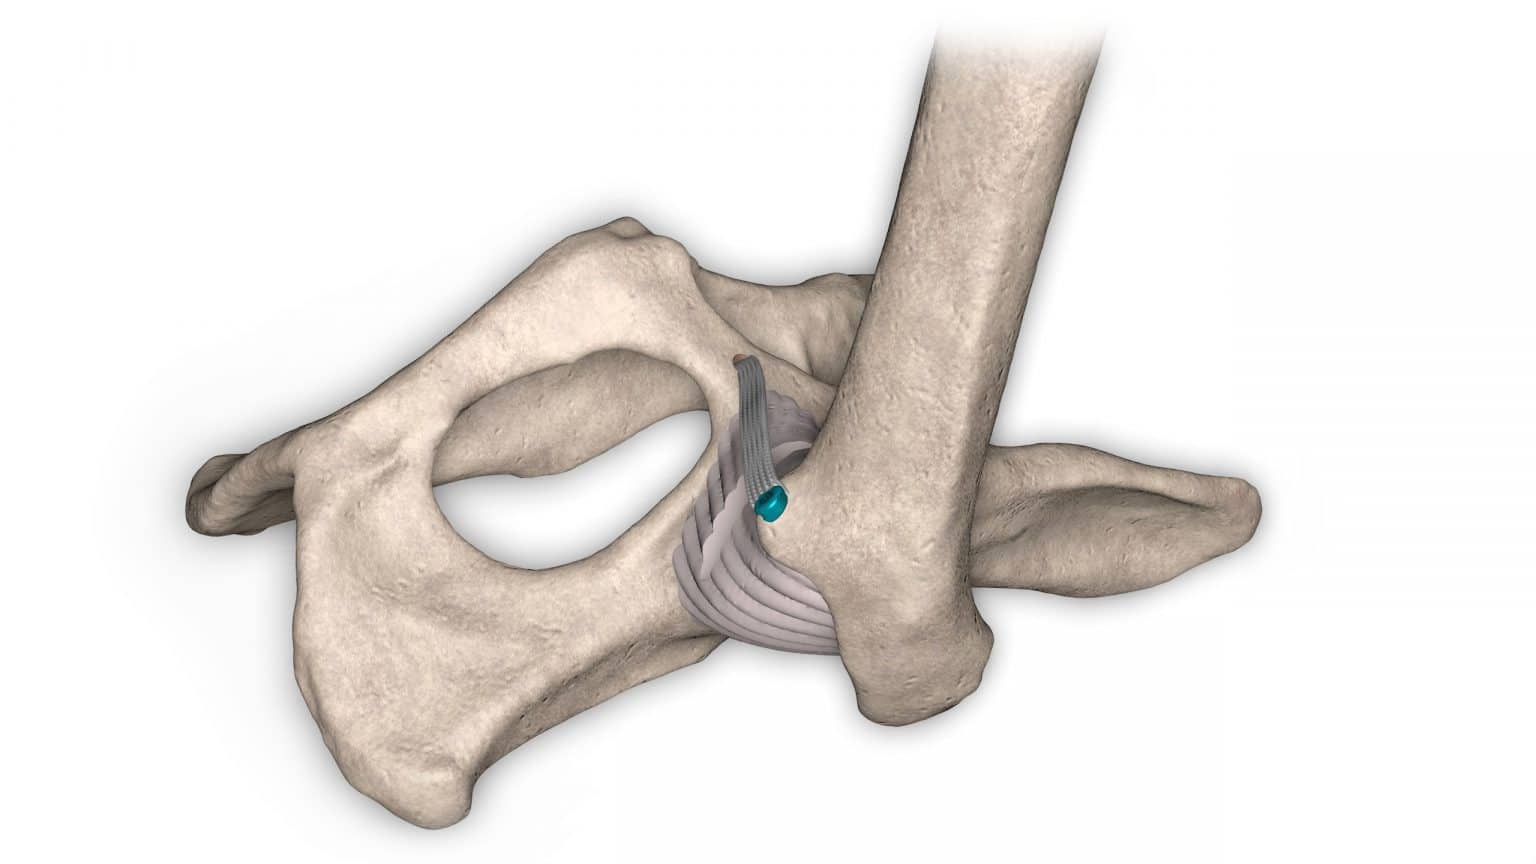

V případě ruptury kraniálního zkříženého vazu umožňuje ExtraTape® extraartikulární rekonstrukci co nejblíže izometrii původního vazu, čímž rychle a trvale stabilizuje koleno bez uzlů a zvlnění, což je slabina tradičnějších technik extraartikulární stabilizace. Ty jsou zde nahrazeny pevným ukotvením kosti pomocí interferenčního šroubu.